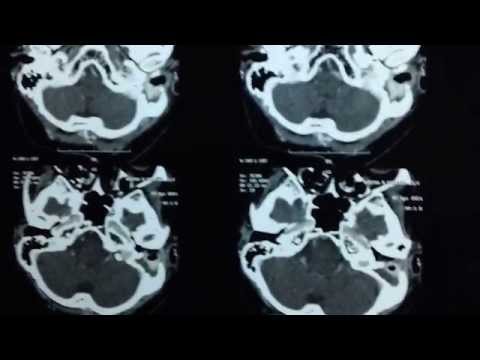

Facial Nerve Weakness_CT Scan Mastoid Bone

Face Paralysed after Ear Infection

Facial nerve paralysis can be seen in patients who suffer from acute and chronic ear infections (otitis media). Sudden facial paralysis in chronic ear disease suggests damage caused by pressure on the nerve by cholesteatoma sac as in this case. When this happens prompt surgical exploration with evacuation of disease and nerve decompression usually results…

Mastoid Operation-Cholesteatoma-Trivandrum India

Large or complicated cholesteatomas like this one always require surgical treatment to protect the patient from serious complications. Mastoidectomy surgery is performed under general anesthesia . The primary purpose of the surgery is to remove the cholesteatoma and infection and achieve an infection-free, dry ear. This is done in Jubilee Christian Mission Hospital Trivandrum Kerala…